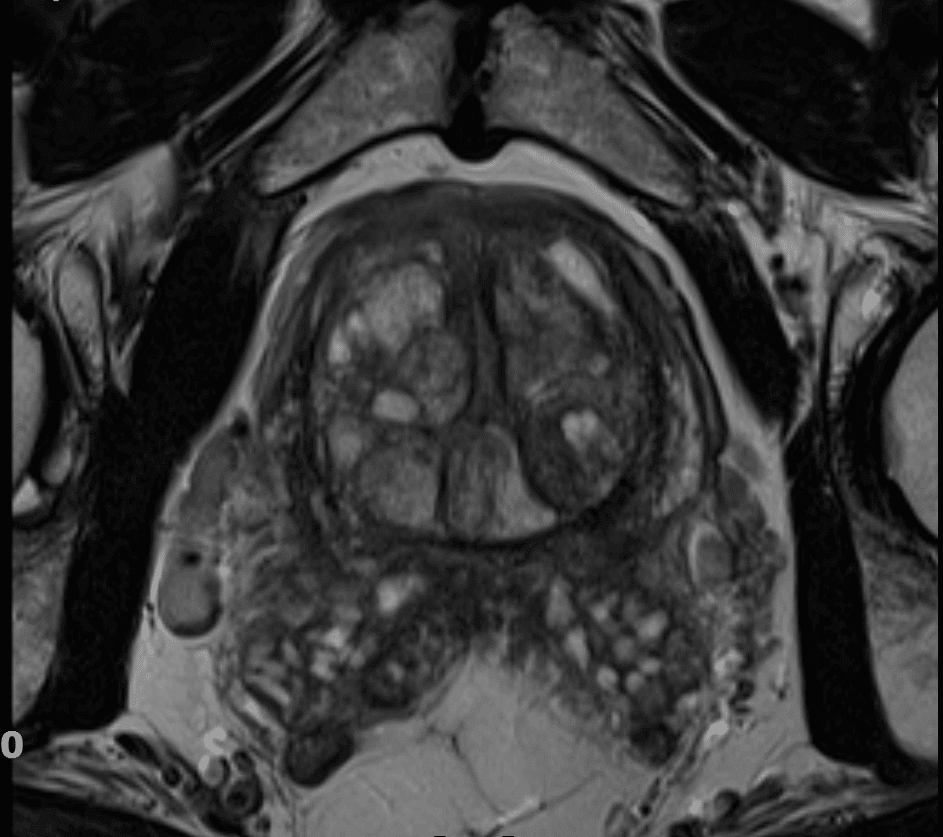

Magnetska rezonancija prostate

Trenutačno najsuvremenija dijagnostička metoda za rak prostate je magnetska rezonancija na MR uređaju jakosti 3Tesle. MR prostate na MR 3Tesle možete obaviti u Poliklinici Medikol u Zagrebu i Splitu. Pretraga je za pacijenta potpuno bezbolna i bez ioniziranog zračenja.